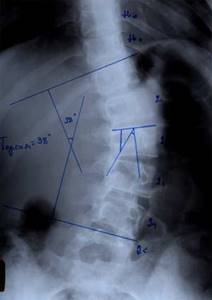

| Больной П-ко, 15 лет Поясничный сколиоз III степени |

Результат оперативного лечения |